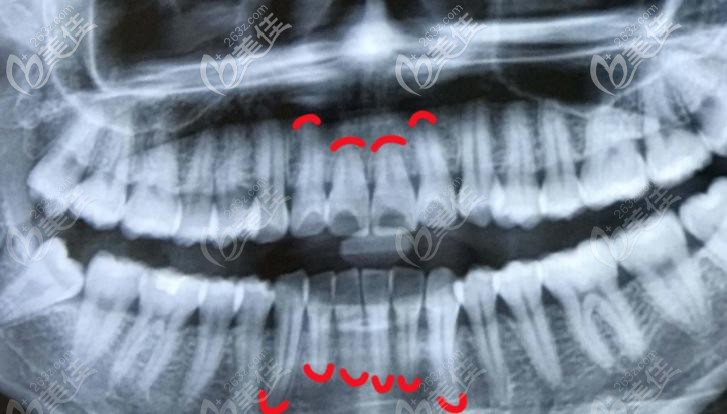

为了进一步加强牙周诊疗的技术,福州登特口腔特别举办了“标准化的牙周刮治”技术交流大会,让更多人的医护人员以及顾客了解牙周病的发生原因、治疗方法以及如何预防。